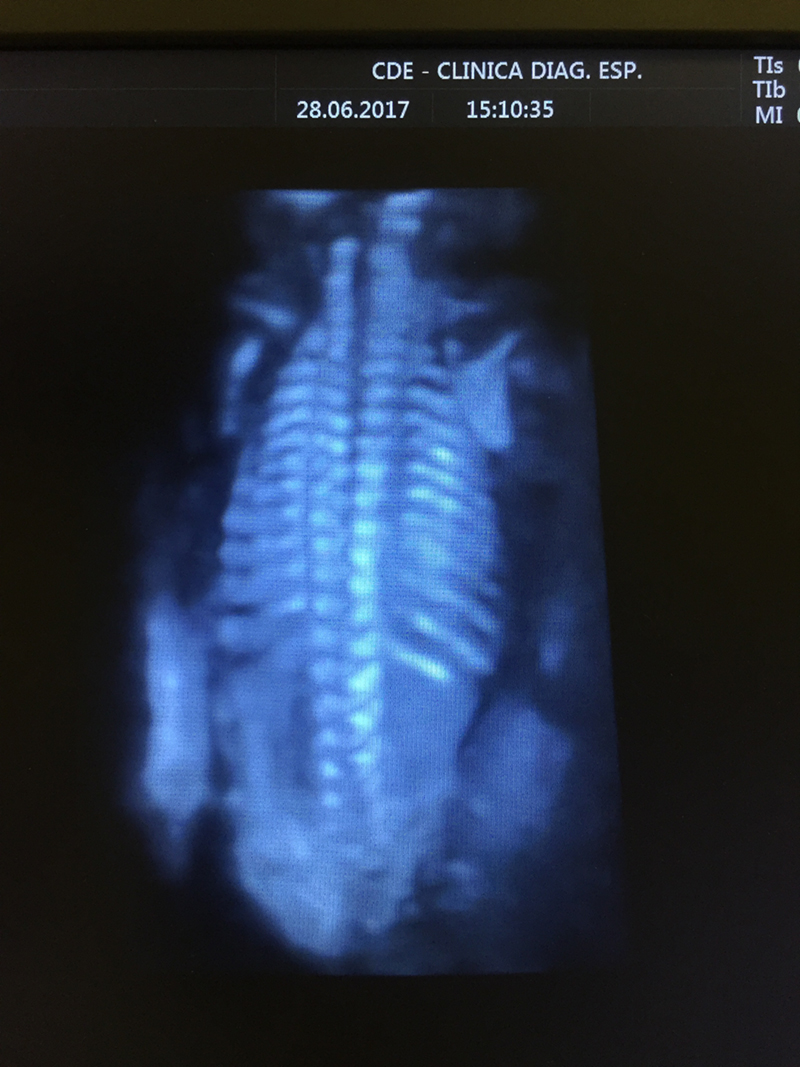

- Ultrassonografia Tridimensional 4-D;